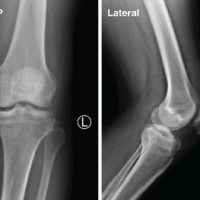

A 34-year-old male presented to our outpatient department with complaints of chronic right ankle pain and difficulty bearing weight for the past several months. He gave a history of a high-velocity RTA 6 months ago, following which he was diagnosed with a talus fracture and managed conservatively with immobilization and non-weight-bearing protocol at another center. The patient resumed weight-bearing pre-maturely due to socioeconomic constraints. Clinical examination revealed mild swelling, tenderness over the anterolateral aspect of the ankle, and restricted range of motion. There was no evidence of neurovascular compromise. Plain radiographs of the ankle showed persistent fracture lines in the talar body region (Fig. 1).

Figure 1: Pre-operative X-ray of talus.